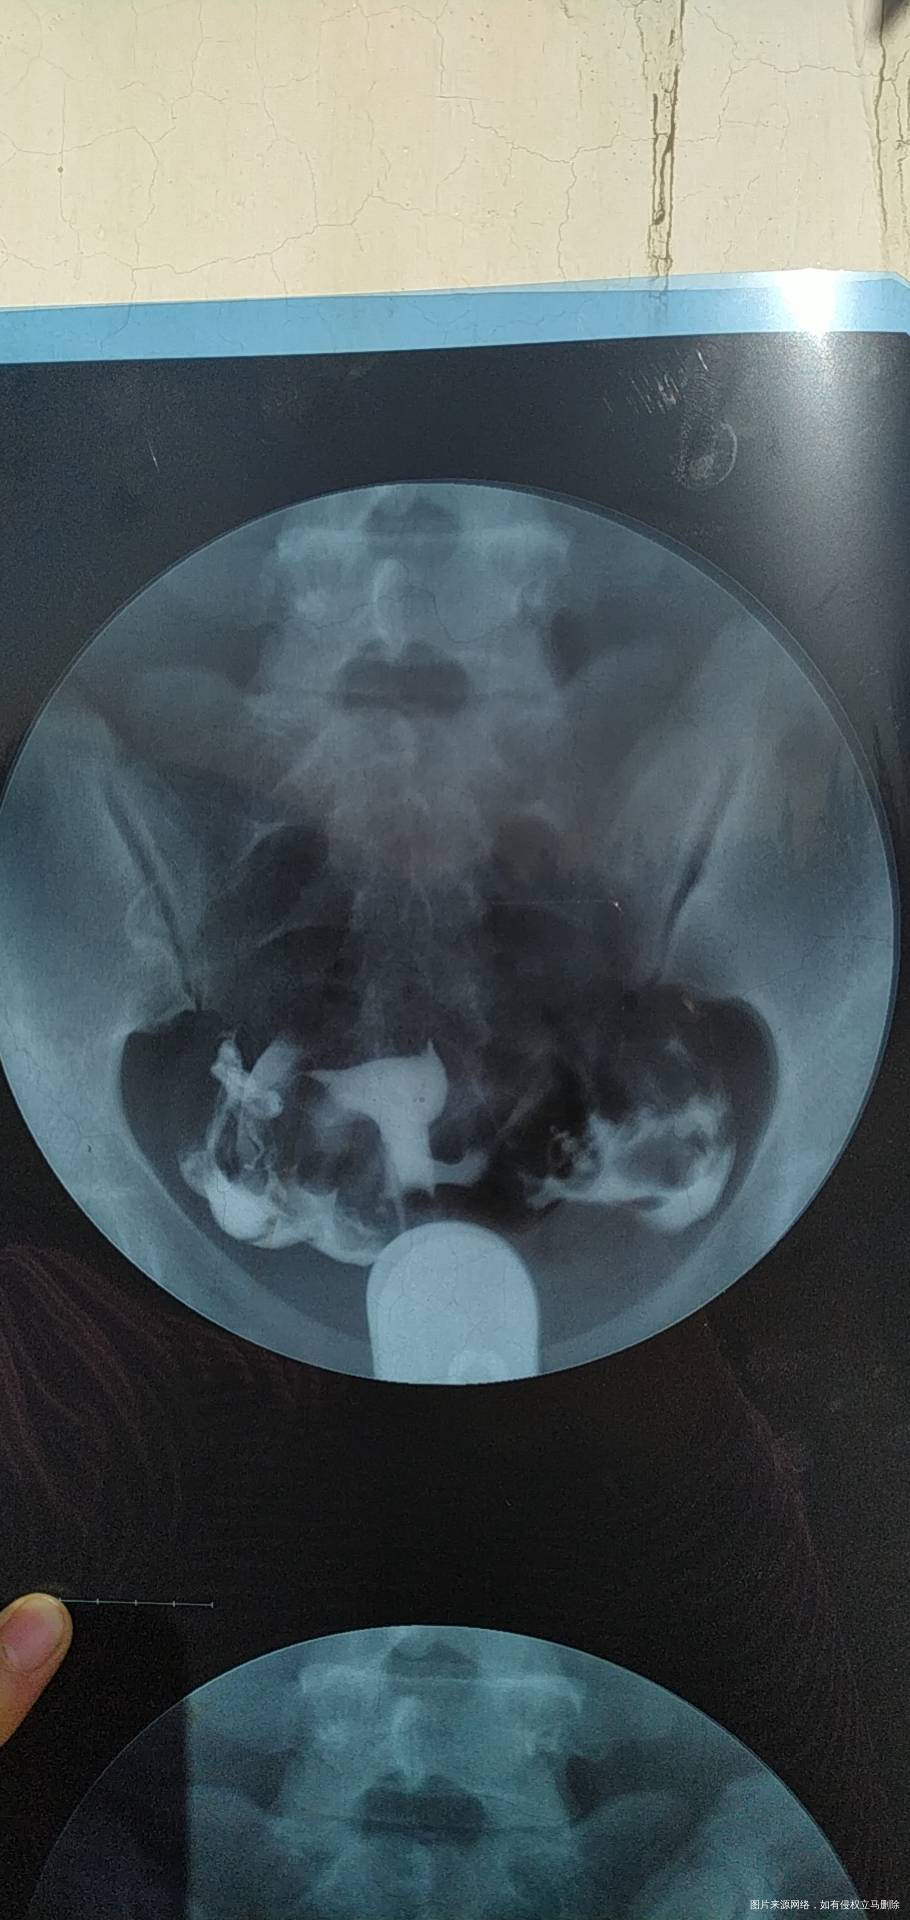

今年七月份做的造影。显示输卵管通而不畅,伴随多囊卵巢,喝中药调理了5个月,促排了两次,均失败。医生建议我直接试管,我想问一下各位专家,我还有自然受孕的机会吗?

亲,输卵管通而不畅不是代表完全不通,还是可以自己试试,多囊卵巢现在有的人太多了。你促排失败是什么原因要找找,胰岛素有抵抗吗,还是血糖油膏?这个内分没问题一般是没事,先可以深继续促排治疗